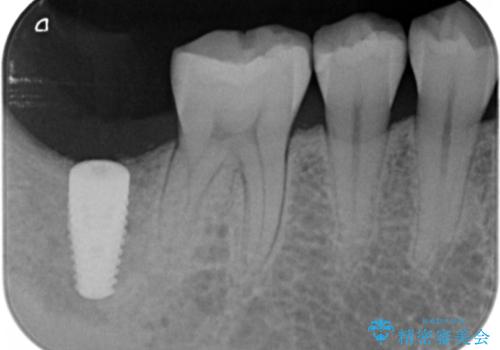

抜歯を行い、インプラントを入れていきました。

炎症で骨が少なかった場所には骨補填材を置いています。

高さがないため、スクリューリテインのインプラントの上部構造にしています。